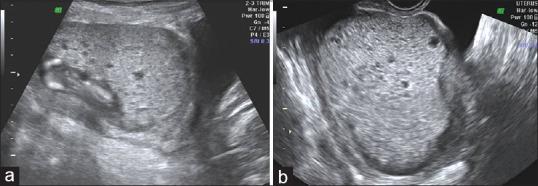

Partial/complete hydatidiform mole with coexisting fetus is a rare condition. Optimal management is a challenge that remains a dilemma since these pregnancies are associated with maternal as well as fetal complications including hemorrhage, preeclampsia, thromboembolic disease, intra uterine demise and increased risk of persistent trophoblastic disease. Here we report 2 cases of partial mole with live fetus after ICSI and a case of complete mole with coexisting fetus after ICSI in a turner mosaic that resulted in a live birth.

部分性/完全性葡萄胎合并存活胎儿是一种罕见情况。最佳管理是一项挑战,仍然是一个两难困境,因为这些妊娠与母体和胎儿并发症相关,包括出血、先兆子痫、血栓栓塞性疾病、宫内死亡以及持续性滋养细胞疾病风险增加。在此,我们报告2例经卵胞浆内单精子注射(ICSI)后部分性葡萄胎合并存活胎儿的病例,以及1例经ICSI后完全性葡萄胎合并存活胎儿的病例,该病例为特纳综合征嵌合体,最终成功分娩。